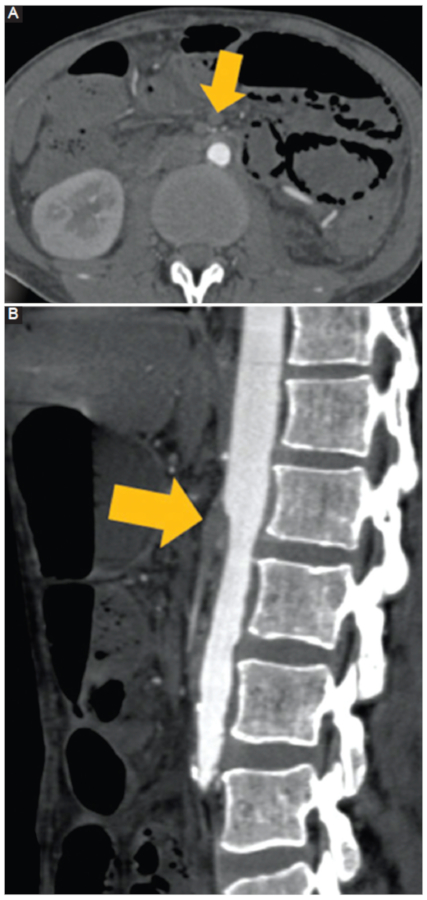

Enfermedad arterial inducida por radiación: la radioterapia es un tratamiento aceptado mundialmente y utilizado en el tratamiento de las neoplasias. Sin embargo, existe un daño a estructuras adyacentes que resulta a veces inevitable. Este daño ocurre por dos mecanismos: primero, por daño celular directo por parte de la radiación; segundo, por los radicales libres producidos a consecuencia de esta, lo que puede provocar daño en estructuras vasculares17. En este contexto clínico podemos observar, a nivel de las estructuras vasculares, la presencia de trombosis, rotura arterial, fibrosis, estenosis arterial y fenómenos ateroescleróticos locales acelerados (Fig. 11). Es fundamental conocer la historia clínica del paciente para poder considerar esta etiología como la responsable del daño arterial.

Figura 11

Enfermedad arterial inducida por radiación. Hombre de 40 años con antecedente de cáncer testicular a los 20 años, tratado con radioterapia y cirugía. TC con contraste. A: corte axial en fase arterial. B: corte sagital en fase arterial. Se observa un trombo oclusivo de la arteria mesentérica superior desde su origen (flecha).